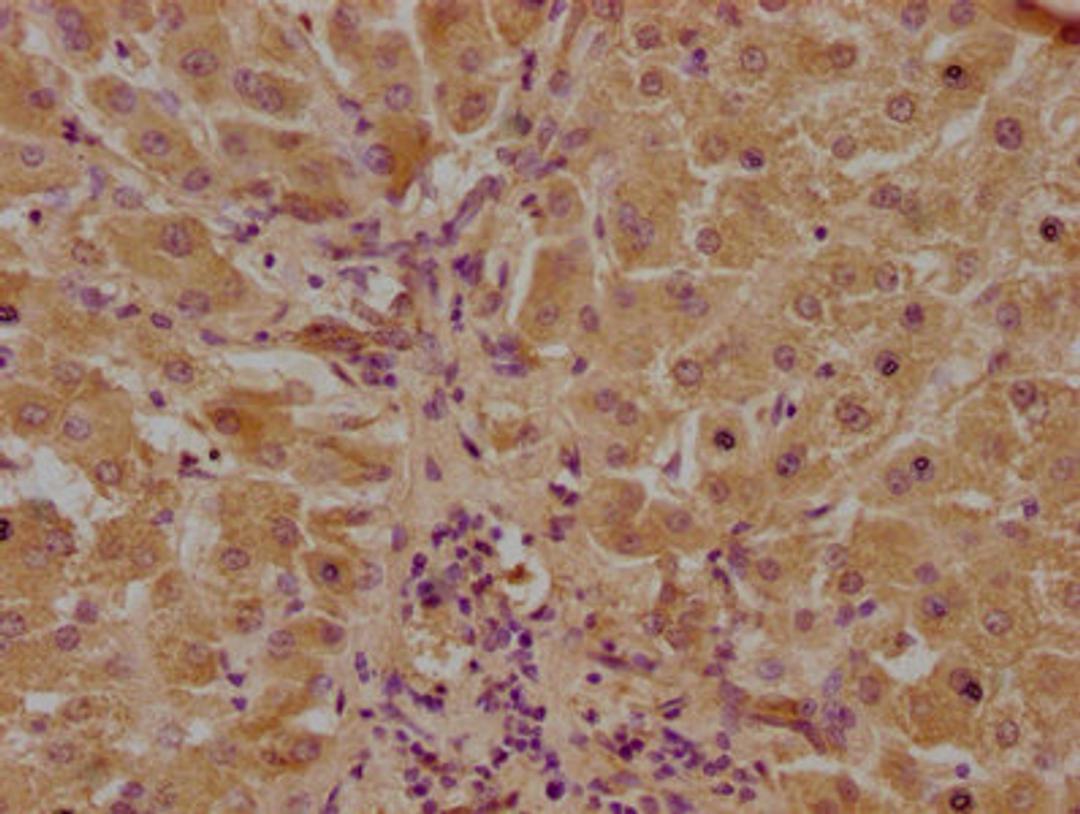

IHC image of CSB-PA811601LA01HU diluted at 1:100 and staining in paraffin-embedded human liver tissue performed on a Leica BondTM system. After dewaxing and hydration, antigen retrieval was mediated by high pressure in a citrate buffer (pH 6.0). Section was blocked with 10% normal goat serum 30min at RT. Then primary antibody (1% BSA) was incubated at 4°C overnight. The primary is detected by a biotinylated secondary antibody and visualized using an HRP conjugated SP system.